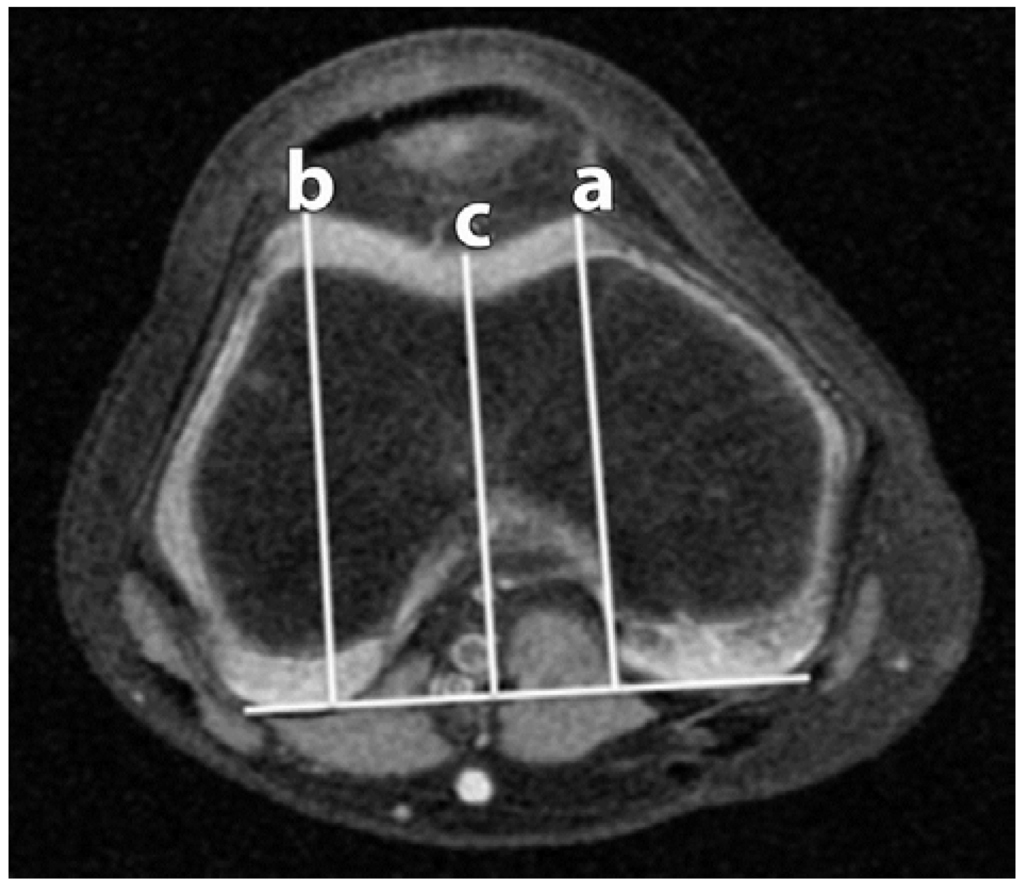

Figure 3.

Trochlear Depth (TD). A posterior condylar reference line is created (solid white line). Three lines are drawn from the reference line to the lateral facet apex (b); medial facet apex (a); and the deepest portion of the sulcus (c).